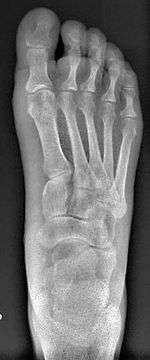

Syndesmosis procedure addresses specifically the two fundamental problems of metatarsus primus varus deformity that gives rise to the bunion deformity. They are leaning and instability of the first metatarsal bone . Syndesmosis procedure uprights the leaning first metatarsal bone with strong binding sutures between it and the second metatarsal bone (Fig. 2) and then also stabilizes it uniquely by creating a fibrous connecting bridge between these two bones (Fig. 3,4). First metatarsal bone can be readily realigned is because by definition of the metatarsus primus varus deformity its first metatarsal is abnormally loose and mobile.